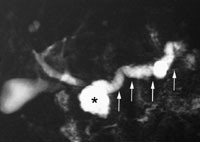

Tre pasienter, mistenkt for kronisk pankreatitt, ble undersøkt med S-MRCP. To fikk påvist typiske kalibervekslinger i pancreasgangen (fig 2), funn som økte sannsynligheten for diagnosen kronisk pankreatitt. De er fulgt i åtte og 20 måneder, uten at noe tegn til malignitet er påvist. Den tredje pasienten med pankreatitt fikk påvist pancreas divisum, som ikke tidligere var erkjent ved ERCP av grunner nevnt ovenfor.

Ved stenoser i pancreasgangen er det et klassisk problem å skille maligne stenoser fra residiverende eller kronisk pankreatitt (7, 8). Det er angitt kriterier for å vurdere forandringer som skyldes kronisk pankreatitt ved S-MRCP (9, 10). I vår undersøkelse har disse kriteriene gitt økt sannsynlighet for å stille denne diagnosen. Allikevel kan vi ikke ut fra de første pasientene vi undersøkte med S-MRCP på denne problemstilling sikkert si om metoden klart kan skille mellom benigne og maligne stenoser.